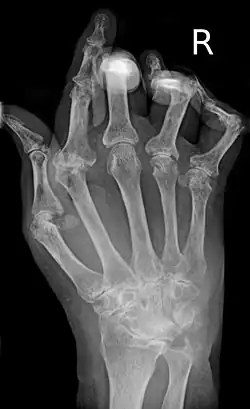

| A hand severely affected by rheumatoid arthritis. This degree of swelling and deformation does not typically occur with current treatment. | |

As the pathology progresses, the inflammatory activity leads to tendon tethering and erosion and destruction of the joint surface, which impairs range of movement and leads to deformity. The fingers may develop almost any deformity depending on which joints are most involved. Specific deformities, which also occur in osteoarthritis, include ulnar deviation, boutonniere deformity (also "buttonhole deformity", flexion of proximal interphalangeal joint and extension of distal interphalangeal joint of the hand), swan neck deformity (hyperextension at proximal interphalangeal joint and flexion at distal interphalangeal joint) and "Z-thumb." "Z-thumb" or "Z-deformity" consists of hyperextension of the interphalangeal joint, fixed flexion, and subluxation of the metacarpophalangeal joint and gives a "Z" appearance to the thumb.[16]: 1098 The hammer toe deformity may be seen. In the worst case, joints are known as arthritis mutilans due to the mutilating nature of the deformities.[20]